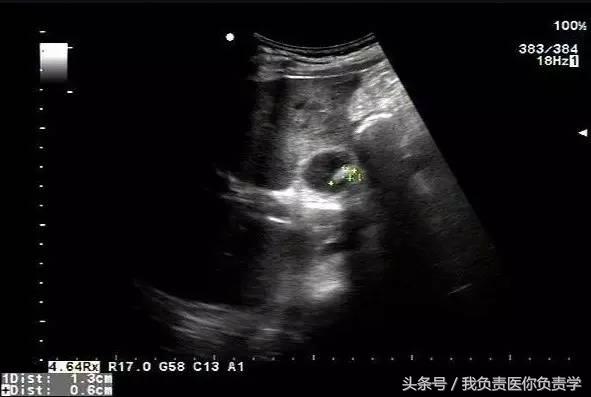

典型病例 4

患者女,79岁,晚餐后出现脐周疼痛数小时急诊。患者无发热,实验室检查示白细胞14×109/L,临床考虑阑尾炎,行超声检查所见如下:

图1示胆囊充盈差,囊壁明显增厚,胆囊周围可见无回声环绕分布

图2为高频探头所见,示胆囊壁肝床侧回声中断,周围可见无回声分布

超声诊断为胆囊穿孔,后经手术证实。